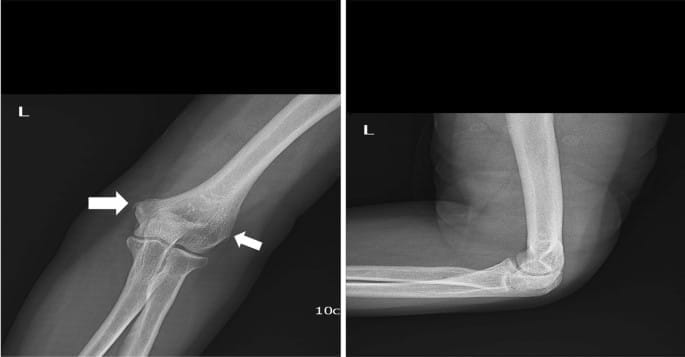

To diagnose an elbow fracture, doctors use:

- X-rays: Standard imaging to see the bone structure and identify fractures.